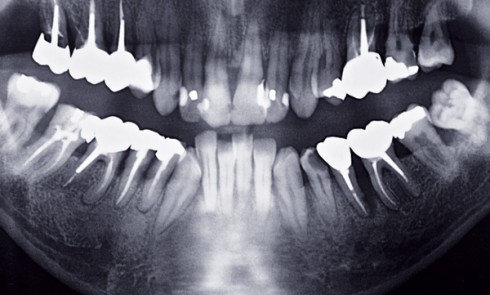

Article réservé à nos abonnés Atrophie maxillaire extrême

La chirurgie pré-implantaire est bien décrite [1] et peut consister en des greffes d’apposition et/ou des comblements sinusiens avec des...